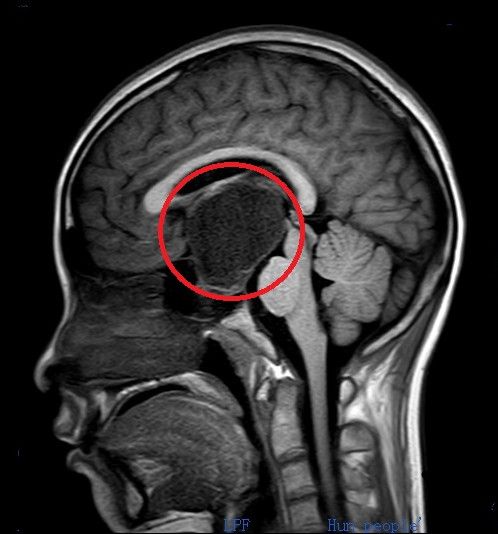

术前头部ct和核磁共振检查显示:鞍区肿瘤(红圈内)比乒乓球还大,并压迫周围重要的神经和血管。

入院后进一步检查发现,肿瘤约为4.5×4.4×4.6cm,比乒乓球还大,周围遍布颈内动脉、视神经、三脑室底、海绵窦、垂体、垂体柄等重要的神经和血管。医生告诉小雯和家属,由于肿瘤压迫视神经,因此导致她视力减退;还压迫垂体,导致其内分泌紊乱、月经失调,并形成颅高压。如不尽快手术,病情继续进展可能危及生命。